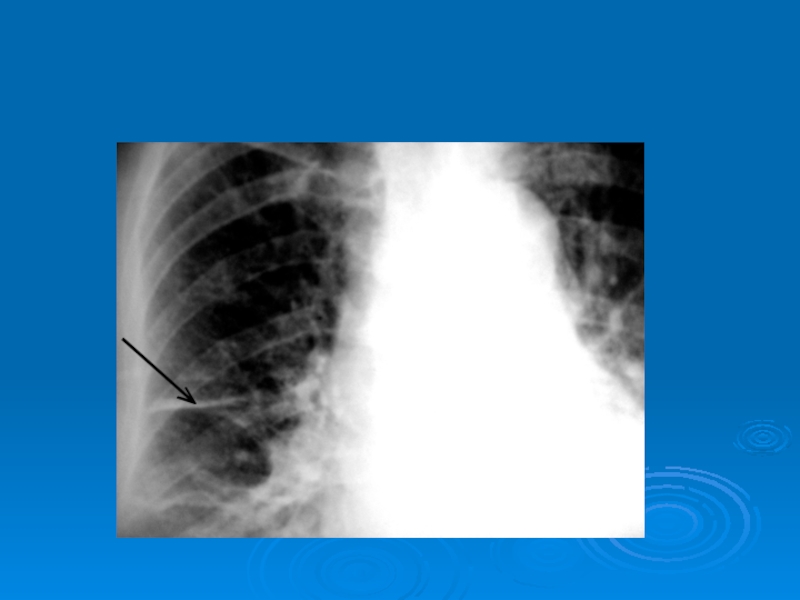

Слайд 33Затемнение части легочного поля. Центральный рак правого легкого

Затемнение части легочного поля. Центральный рак правого легкого